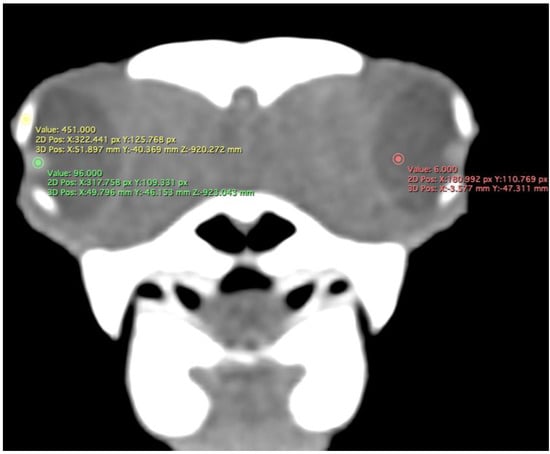

- Attenuation of the sclerotic ring and lens, taken in the dorsal area and vitreous humour expressed in Hounsfield Units (HU) (Figure 4).